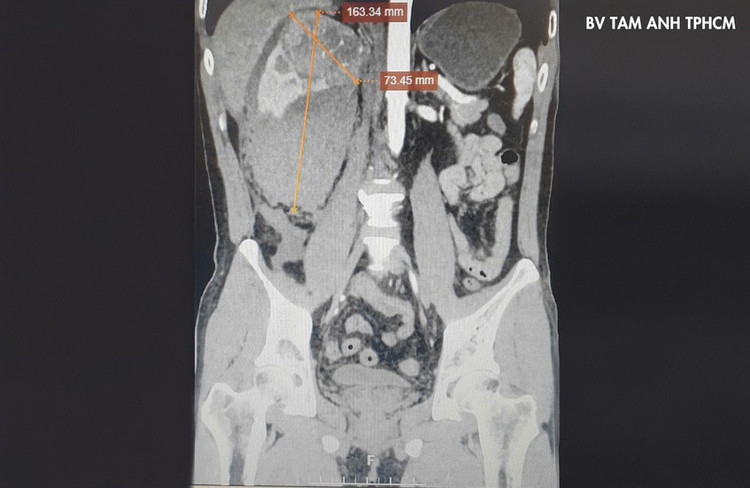

Một tuần trước, anh Nam, 43 tuổi đến Bệnh viện Đa khoa Tâm Anh TP HCM do đột ngột lên cơn đau ở vùng hông lưng phải, siêu âm thấy bất thường ở thận, bác sĩ chỉ định chụp CT thấy một khối u ở thận phải, kích thước 8cm có tình trạng xuất huyết rất nguy hiểm, nghi ngờ u ác tính.

Khối u của anh Nam ở thận phải, kích thước 8cm có tình trạng xuất huyết rất nguy hiểm. Ảnh: BVCC